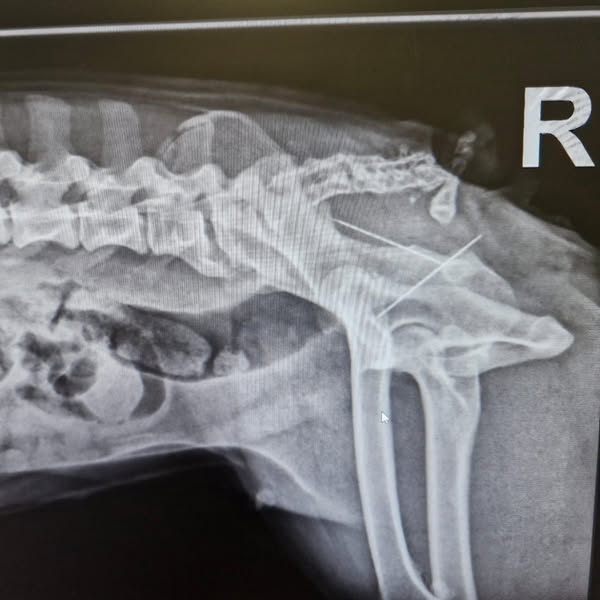

Immer wieder kommt es zu grausamen Vorfällen mit ausgelegten Gift- oder Fremdkörperködern. Aktuell gab es einen besonders erschütternden Fall: Eine französische Bulldogge musste notoperiert werden – in ihrem Rektum befanden sich zwei Nähnadeln. Die Nadeln konnten entfernt werden und die Hündin ist wohlauf.

Eine Nadel hatte bereits die Schleimhaut durchbohrt und war in die Muskulatur eingedrungen, die andere lag im Darmlumen. Ein solcher Vorfall verursacht nicht nur extreme Schmerzen, sondern kann schnell lebensbedrohlich werden.